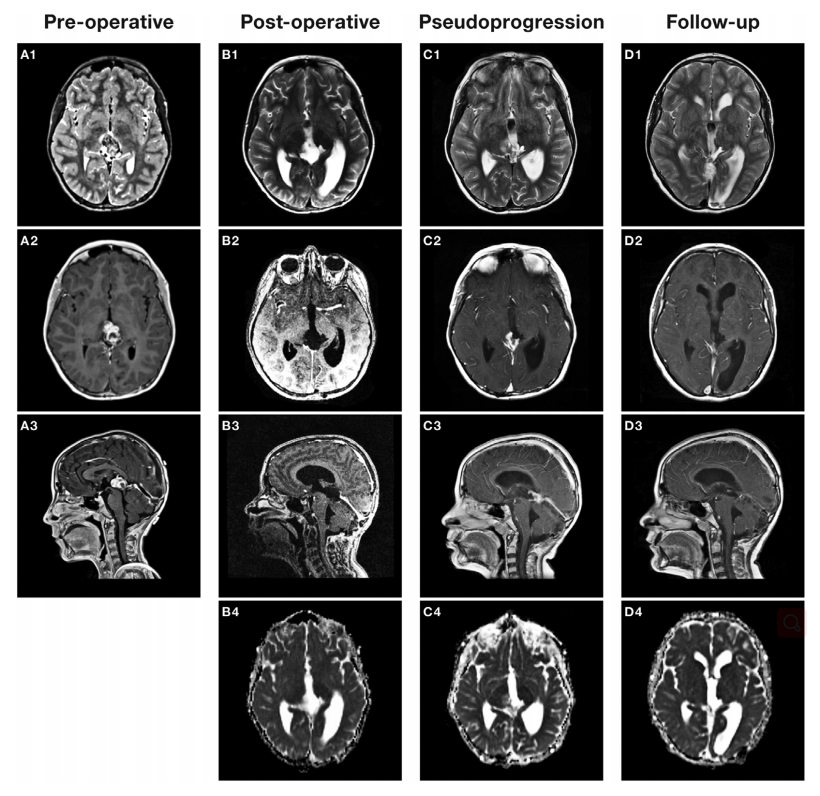

1例9岁男童,具有自闭症谱系障碍、选择性缄默症和成熟型糖尿病的背景,表现为颅内压升高的迹象。磁振造影显示一个不均匀的实性囊性松果体肿瘤,强烈增强,引起脑积水。该儿童接受了内镜下三脑室造口术(ETV)和插入Rickham水库之后,松果体肿瘤的切除。较初的组织病理学诊断与畸胎瘤一致,有1%的不成熟成分(图1)。

切除肿瘤后的三个月,常规监测影像显示残留肿瘤有重新生长。对潜在的辅助治疗进行讨论后,考虑到随访扫描中残余肿瘤的进一步增大,多学科决定进行较大限度的顺利切除(图1A)。一开始并无大碍的手术在切除的较后阶段因术中脑肿胀而变得复杂,推测是由于脑室系统的隐匿性出血。快速切除完成,腔内填充止血材料。术后即刻影像学检查证实脑室内出血,内镜冲洗及再做etv检查。术后患者表现为后颅窝综合征,吞咽功能受损,需要胃造口进食,左脑梗死并残余偏瘫。

术后MRI证实全部切除(图1B)。组织学显示有5%的生殖细胞瘤成分的成熟畸胎瘤(图1);事后看来,在较初的标本中观察到的小的未成熟区域也被证实是生殖细胞瘤的组成部分。头部/脊柱MRI扫描或脑脊液细胞学检查未发现软脑膜播散。血液中连续肿瘤标记物从较初表现开始呈阴性。据然而辅助治疗CNS GCT II试验(NCT01424839)局部的生殖细胞瘤是根据两个周期患者的辅助卡铂/依托泊苷,紧随其后的是整个脑室放疗(24 Gy, 15分数)与容积旋转调强放疗(16 Gy, 10分数)治疗。

放疗后6周,常规MRI显示切除腔内轻微线性强化。放射治疗后4个月,松果体区强化病灶的大小进一步增加,弥散特征与原发肿瘤相似,提示局部复发(图1C)。当时没有进行磁共振波谱或其他功能磁共振成像序列研究。患儿临床表现稳定,无新症状。在与该家庭讨论了全部可能的结果后,考虑了观察和等待的方法。

放射治疗后8个月的MRI扫描显示肿瘤床内的造影剂增强组织减少,在随后的随访中在没有类固醇或任何其他额外治疗的情况下完全消失。放疗后25个月的较新mri扫描显示持续的完全缓解(图1D)。孩子已经恢复得很好,吞咽正常,没有神经功能障碍。